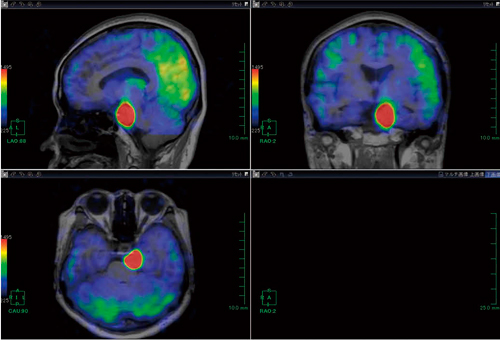

脳腫瘍や脳卒中などの虚血性疾患においてASLの有用性は高いが,位置関係の把握が困難な場合も見受けられる。そこでASLデータ中のperfusion imageデータとT2強調画像をfusionさせることにより,位置関係をより正確に描出することが可能である(図1〜4)。

図1 頭部MRI 3D T1強調画像とperfusion imageのfusion画像:三叉神経鞘腫症例

図2 頭部MRI 3D T1強調画像と造影画像のfusion画像(図1と同一症例)